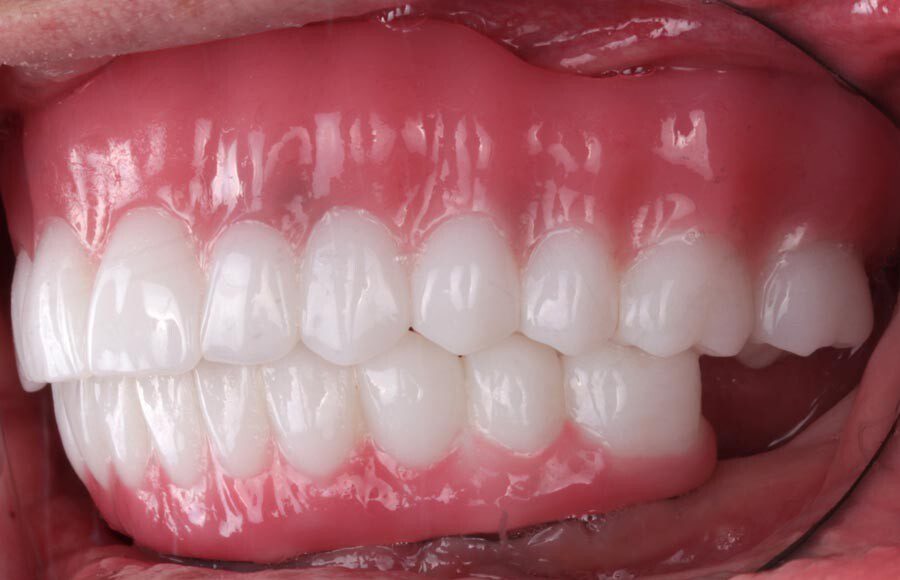

Smile GalleryImplant RestorationsImplant Dentures Post-op smiling 1 of 32 Pre-op close up smiling Pre-op lips retracted smiling Pre-op panoramic x-ray Implants in upper jaw (occlusal view) Implants in lower jaw (occlusal view) Panoramic x-ray of implants First set of try-ins – upper denture First set of try-ins – lower fixed provisional Delivered try-ins (lips retracted) Close adaptation to gums and appropriate emergence profile of lower fixed provisional Gum tissues have been molded by a convex provisional Delivered try-ins Second set of try-ins (lips retracted) Close adaptation to gums and appropriate emergence profile of second set of lower fixed provisional Delivered second try-ins Definitive restorations on casts (frontal view) Definitive restorations on cast (right side) Definitive restorations on cast (left side) Definitive upper overdenture (occlusal view) Definitive lower fixed titanium-acrylic hybrid restoration (occlusal view) Definitive lower fixed titanium-acrylic hybrid restoration (frontal view) Definitive lower fixed titanium-acrylic hybrid restoration (tissue side view) Healthy molded gum tissues on lower prior to delivery of lower fixed hybrid restoration Healthy gum tissues on upper prior to delivery of upper overdenture Definitive restorations (frontal, lips retracted) Definitive lower restoration (frontal) Definitive restorations (right side) Definitive restorations (left side) Definitive lower restoration (occlusal view) Definitive upper restoration (occlusal view) Post-op panoramic x-ray Post-op smiling